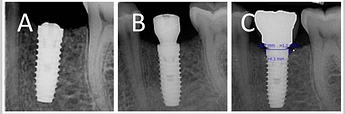

Crestal implant: (A) baseline (B) three months after placement (C) three months after loading

Subcrestal implant: (A) baseline (B) three months after placement (C) three months after loading